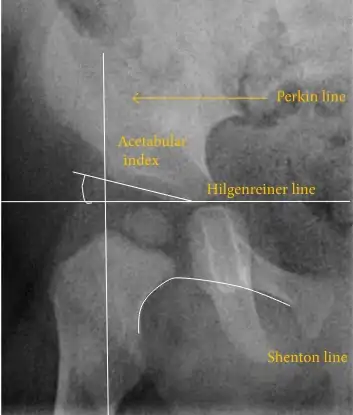

Despite the widespread use of ultrasound, pelvis X-ray is still frequently used to diagnose or monitor hip dysplasia or for assessing other congenital conditions or bone tumors.[45]

The most useful lines and angles that can be drawn in the pediatric pelvis assessing hip dysplasia are as follows:[45] Different measurements are used in adults.[45]